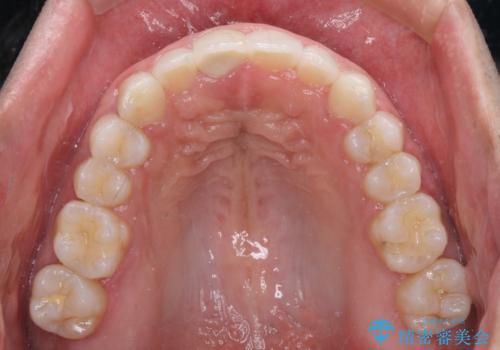

口が閉じにくい インビザラインによる矯正治療

- 口の閉じにくさを気にして来院された患者様です。

患者様と相談の上、横顔の印象から抜歯矯正は必要ないと判断し、IPR(歯と歯の間)並びに歯列全体の後方移動により口元の突出感の改善することとしました。

しっかりと装着時間を守り、ゴムかけも徹底していただいたので、思いの外口元を引っ込めることができました。

これ以上の改善を望まれましたが、非抜歯矯正でこれ以上口元を引っ込めると食いしばりすやすい咬合となるため、この歯列で終了としました。